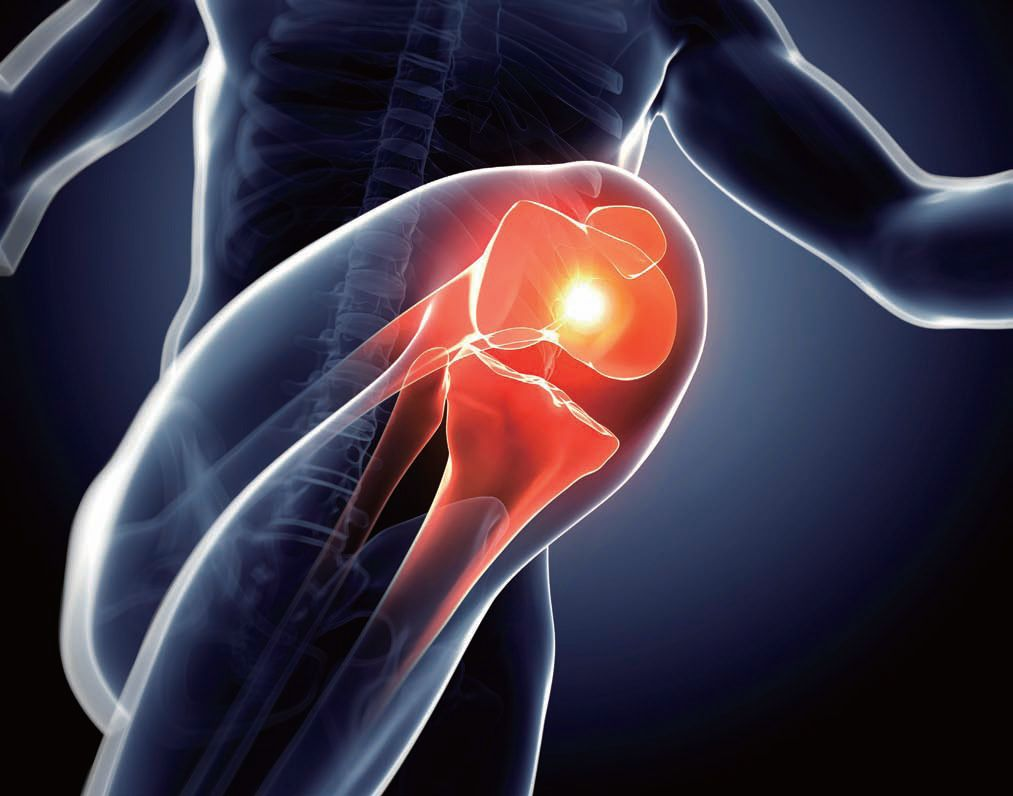

膝盖积液怎么治疗最好的方法,膝盖积液是什么原因造成的。膝盖积液的表现症状和半月板损伤的表现症状如出一辙,但是膝盖积液的问题要小一些,表现为上楼下楼膝盖疼痛,不能弯曲等。下面是jrs直播小编整理的关于膝盖积液的相关资讯,感兴趣的朋友可以了解一下。

1、膝关节内少量积液,可能由于滑膜炎、骨性关节炎或者关节内的半月板损伤、韧带损伤导致,这种情况只需要限制活动,多休息,在配合营养软骨的药物或者是抗炎镇痛的药物,就可以自行吸收,而且正常膝关节内本来就有少量积液,主要是起润滑作用。

2、膝关节内中等量积液或者大量积液,患者会出现膝关节肿胀、疼痛、活动受限等症状,这种情况积液很难自行吸收,需要进行人为用注射器抽出积液,同时向关节腔注射玻璃酸钠,减少关节内的积液。也需要明确是什么原因导致大量积液出现,需要行膝关节MRI检查明确诊断,对病因进行治疗,才能预防膝关节大量积液的再次发生。

膝盖积液最常见的原因就是膝关节里面发生了滑膜炎,最常见的就是因为膝关节本身关节软骨有磨损,增生了骨刺、发生了膝关节的骨关节病。比如说最近活动多了、运动多了、膝盖出现了一些新轻微的外伤之后,会刺激这个骨关节炎急性的发作,急性表现就是滑膜出现了充血、水肿,滑膜会渗出一定的关节液,就是关节积液,这是一个最常见的病因。

还有其他的原因引起,像类风湿性关节炎、痛风性关节炎、大骨节病。像类风湿关节炎它主要是因为滑膜,类风湿关节炎如果达到一个活动期,就会出现滑膜异常的增生,增生之后这个滑膜是个病态的滑膜,也会渗出一些液体,导致关节积液。

对于一些年轻人如果出现突发的膝关节积液,很可能是关节里面出现了一过性的损伤性滑膜炎。还有可能这个积液有可能不是积液,是积血,有些年轻人运动过程当中导致了关节里面的骨挫伤、半月板撕裂、韧带撕裂,就会导致滑膜出血、关节里面积血,这是外伤引起的,膝关节积液主要就是这几个原因引起的。